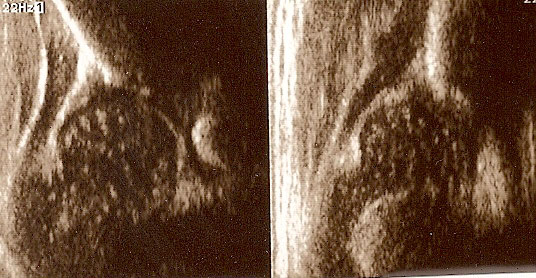

type IIa ( below ) 4 weeks the bony roof is adequate

the bony rim rounded

the cartilage roof cover the head;

the arrows show labrum (red) ;

the bony rim (yellow);

the lower iliac margin (blue) ,

the bony roof line (green) is extends tangential to the lower iliac margin and tangent to the bony rim

the cartilage roof(blue) is drown tangential to the bony rim and through the middle point of the labrum

the baseline (yellow) is drown parallel to ilium echo through the point of the junction of the perichondrium,the periosseum and ilium.

type I (abow) 6 weeks the bony roof is good

the bony rim blunt

the bony roof line (blue) is extends tangential to the lower iliac margin and tangent to the bony rim

the cartilage roof line(green) is drown tangential to the bony rim and through the middle point of the labrum echo ;

asymmetry in the loose joint capsule ,family DDH( when it occurs ask always about it)